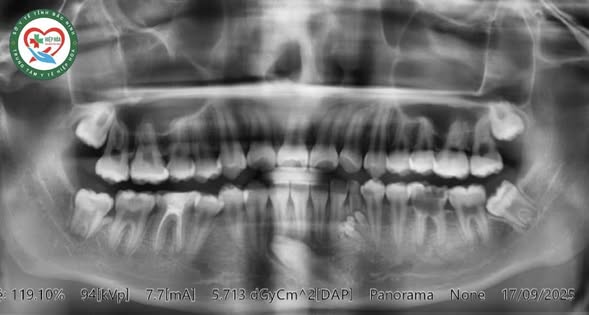

Vừa qua, Trung tâm Y tế Hiệp Hòa tiếp nhận 01 bệnh nhân 15 tuổi có khối sưng bất thường hàm dưới bên trái. Bệnh nhân được chỉ định làm các xét nghiệm, chụp Xquang răng phát hiện có khối u răng đa hợp R33 gây cản trở mọc răng 33 (Thuật ngữ chuyên môn tức là: răng số 3, cung hàm dưới bên trái).

Bệnh nhân được chỉ định phẫu thuật loại bỏ khối u răng. Sau hơn 1 giờ, kíp phẫu thuật do Bs. Đào Thị Ngọc mai, bác sĩ chuyên khoa Răng - Hàm - Mặt, cùng thành viên ê kíp phẫu thuật đã phẫu thuật loại bỏ khối u răng đa hợp R33 cho bệnh nhân. Trong quá trình phẫu thuật, các bác sĩ lấy ra 12 chiếc răng nhỏ tại khối u có đầy đủ thân, tủy và chân răng. Bệnh nhân được phẫu thuật lấy U trên ghế nha khoa dưới gây tê tại chỗ và kiểm soát hành vi.